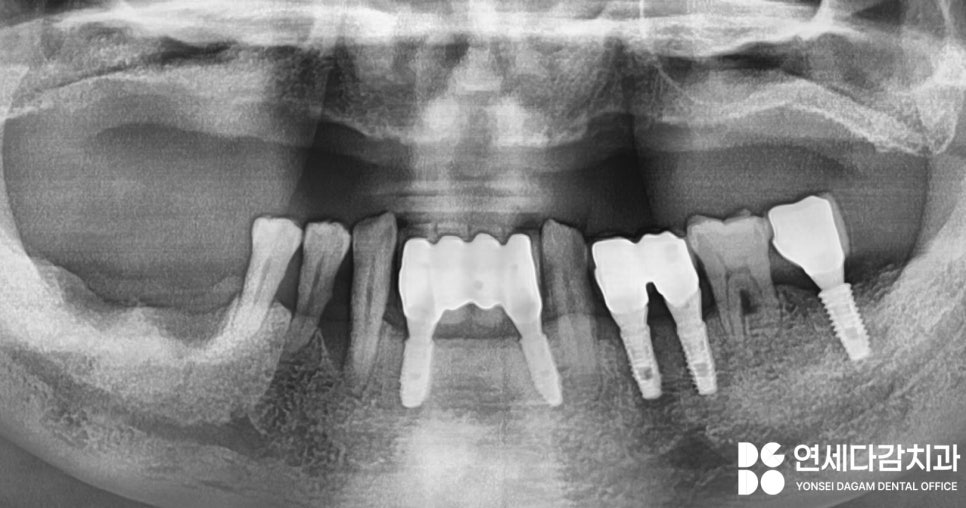

안녕하세요. 가락시장역 연세다감 치과 입니다. 평소 틀니를 쓰고 있었는데 임플란트로 바꾸고 싶으신가요? 상황에 따라서 필요한 치료가 다를 수 있습니다. 어떤 것을 고려해야 되고 보철의 각 장단점을 소개해 드리도록 하겠습니다. 위에는 틀니를 사용하고 있었고 아래턱은 임플란트가 부분적으로 존재하고 있습니다. ...

위에는 틀니를 사용하고 있었고

아래턱은 임플란트가 부분적으로

존재하고 있습니다.

이런 경우 적응을 못할 때가

많습니다.

해당 사례 또한 이가 없는 상태로

오래 지내다 보니 전반적으로

골흡수가 진행된 상태였죠.

전체적인 진단 결과

가락시장역 치과 에서는

임플란트가 적합하다고 생각하였고,

골흡수로 인해 소실된 골의 높이를

뼈이식과 상악동 거상술을 동반한

수술을 통해 충분히 개선될 수

있다고 판단하였습니다.

양측 상악동에 측방 접근법을

통한 거상술을 시행한 뒤,

골이식재를 수복하였고,

총 8개의 픽스처를 식립했습니다.